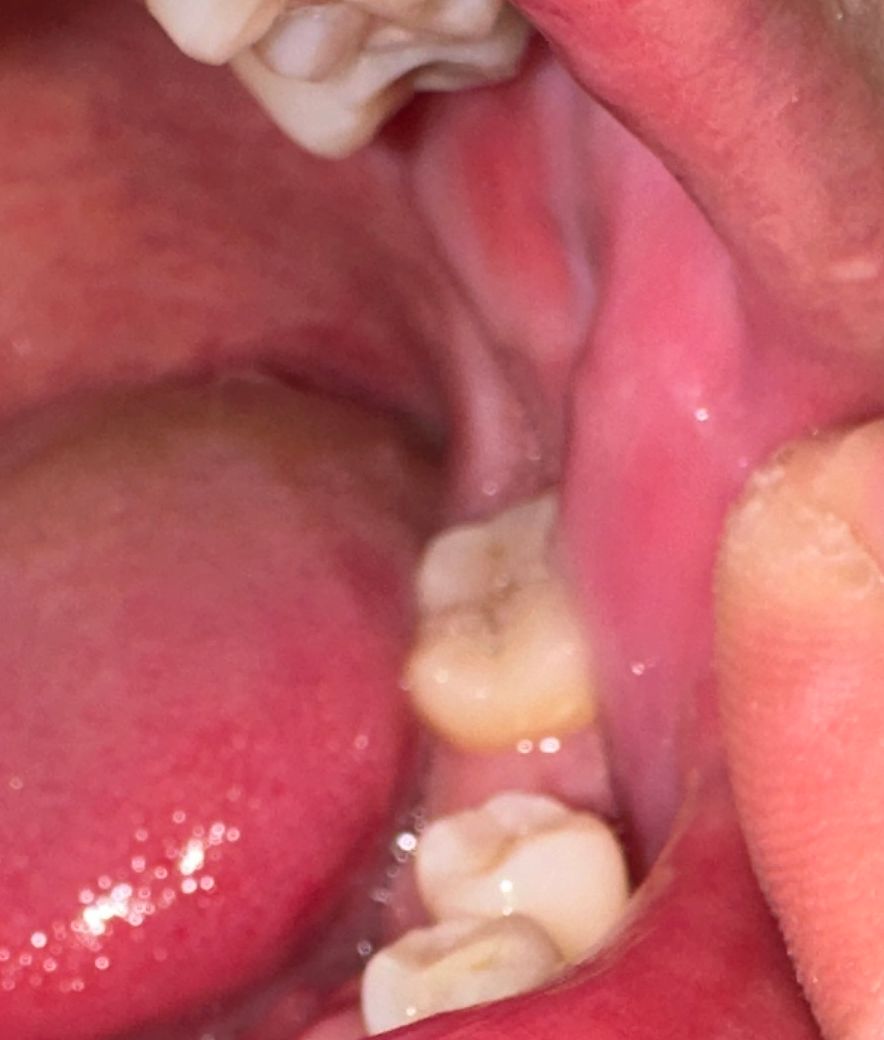

사랑니 발치 후 볼 하얀색같은게 생겼어요

사랑니 발치 후 6일차 입니다. 맥주 두캔정도 먹었는데 볼이 부어서 확인해보니 볼에 하얗게 올라왔습니다.

아픈곳은 없는데 혹시 뭐 때문인가요..

• 2번 째 사진

사진으로는 큰 문제가 보이진 않습니다 음식을 먹을 때 너무 강한 힘이 작용하게 되면 볼 속에 있는 연조직을 치아쪽으로 밀어내면서 하얀색 조직이 생길 수 있습니다 음식을 천천히 먹거나 너무 강한 힘으로 먹지 않는 것이 좋습니다

저부분은 볼살이 치아에 씹혀서 생긴 자국입니다. 큰 문제가 잇는건 아니니 너무 걱정하지 않으셔도 됩니다.

해당부위에 구내염이 발생한 것으로 보이며, 염증이 덧나지 않도록 음주는 피하고, 소독용 가글액인 헥사메딘가글액으로 가글하여 관리하는 것이 증상경감에 도움이 됩니다.